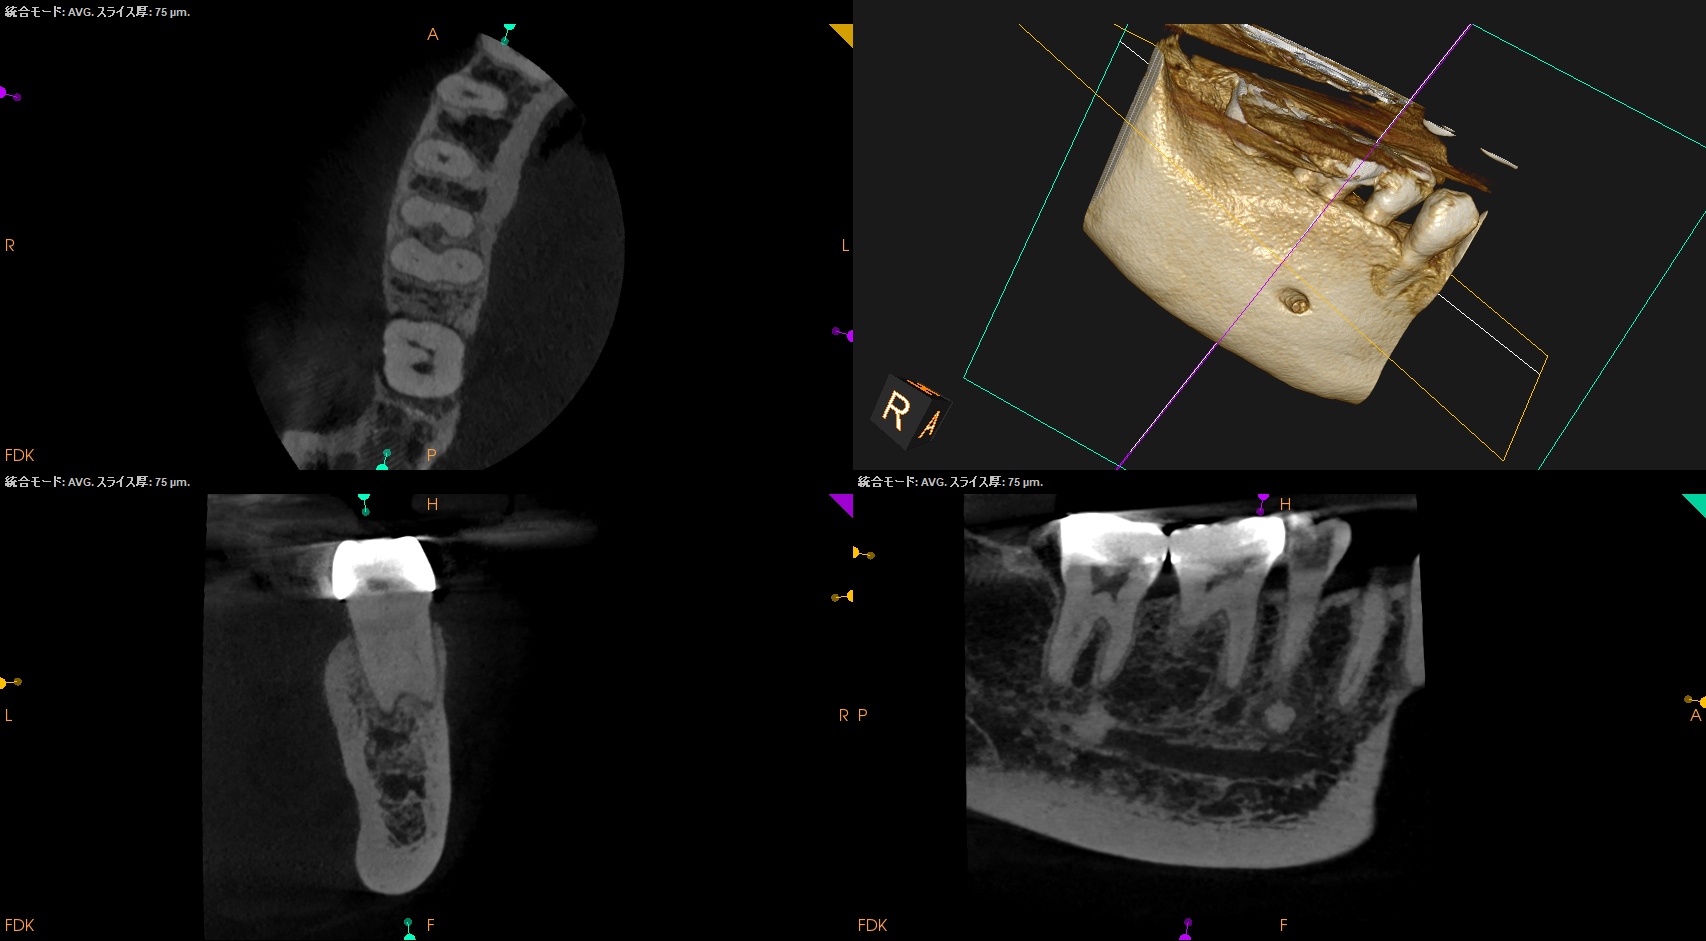

CBCT(2025.5.22)

MB

ML

M根は、

生活歯を歯冠形成したがために、石灰化が進んでおり根管が判然としない。

そして、CBCTでは根尖部に若干の透過像が見られる。

検査からつけ合わせると、おそらく、#30のM根は失活しているのだろう。

D

Radix

D,Radixには病変はないように見える。したがってシーラーパフはこの2根管は起こり得ないということがわかる。

が、それ以前にこれらも石灰化は進んできている。

穿通できるか?は神のみぞ知る話だが、穿通がマストではないと言うことも同時にわかるだろう。

Radixを治療するときには、その根管口がどこにあるのか?予測が必要である。

どうやらRadixの根管口はD根の根管口よりもやや舌側に位置していることがわかる。

そこを見つけられるかどうか?がこの根管を攻略する際のキーだろう。

そして、

今回のRadixはそれほど湾曲は強くないことがわかる。

位置さえ見つかれば、容易にマネージメントができるだろう。